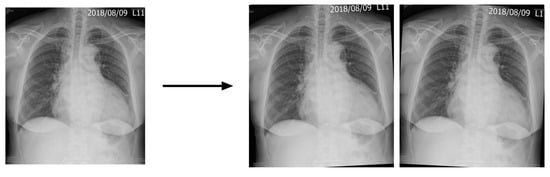

2.4. Image Enhancement